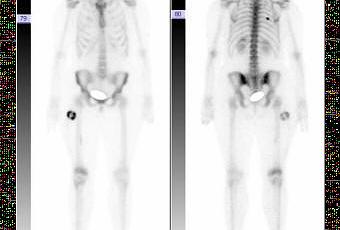

Cuando un médico trata a un paciente el primer paso es evaluar sus síntomas y hacer el diagnóstico. Este paso a veces puede ser trivial. Si te rompes un brazo en la radiografía se ve que el hueso está roto. Además de las fracturas, hay un montón más de lesiones o problemas como tumores, malformaciones que directamente se ven. Los rayos X no son el único método para ver que está pasando dentro del cuerpo. Por ejemplo, la tomografía por emisión de positrones o PET hace uso de la propiedad que tienen las células cancerosas de consumir mucha más glucosa que una célula sana, por lo tanto usando glucosa marcada con radioactividad y un detector se puede determinar si hay alguna parte del cuerpo con una demanda anormalmente elevada de glucosa, que nos indicará un tumor. Un caso similar, pero para huesos, sería las gammagrafias con tecnecio metaestable. Sin necesidad de utilizar radioactividad, la resonancia magnetica nuclear (RMN) nos puede aportar imágenes del interior del organismo aprovechando la propiedad de spin del protón.

Gammagrafia (doi:10.4021/jocmr2010.05.364w)